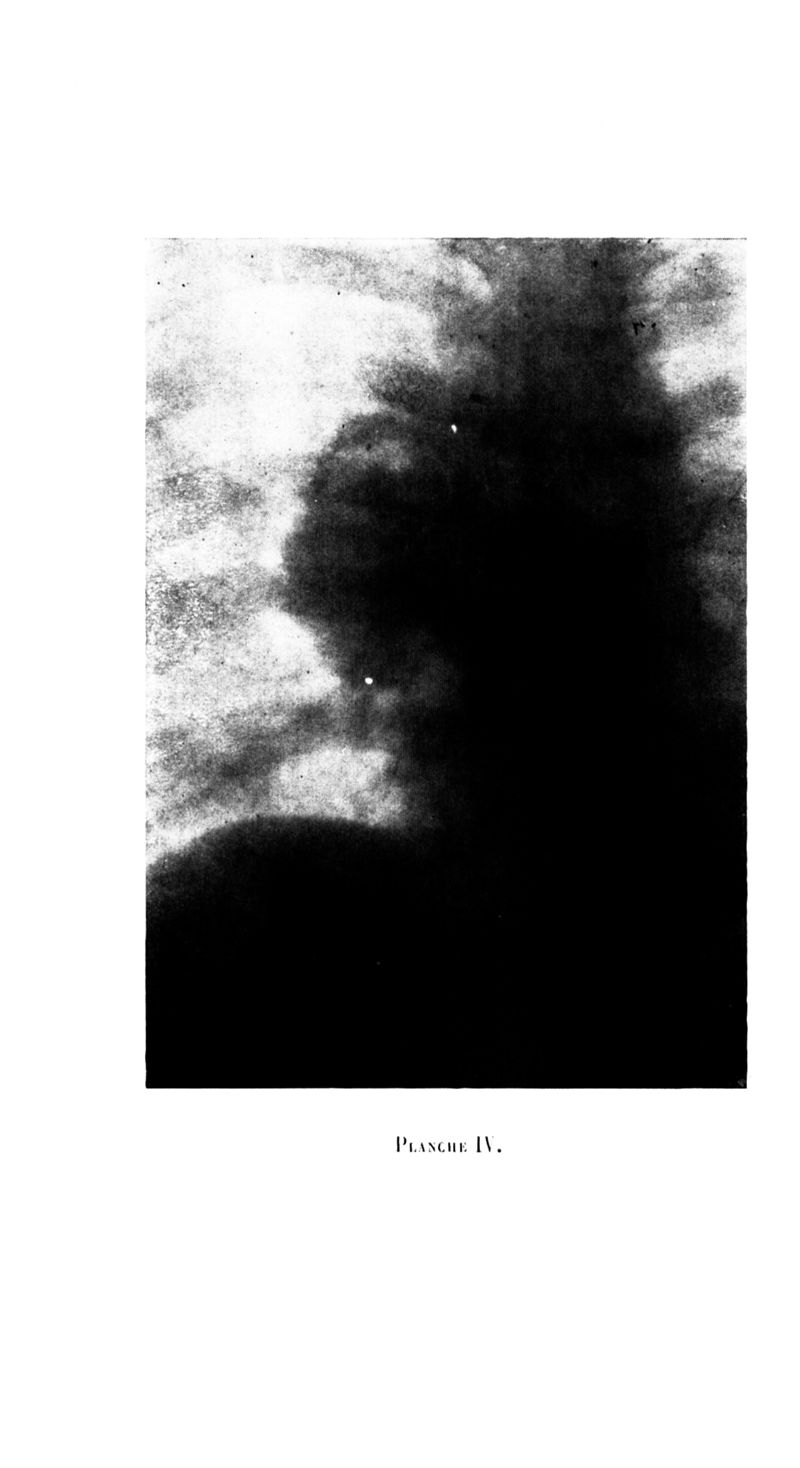

Archives de médecine et pharmacie navales

1924, n° 114. - Paris : Imprimerie nationale, 1924.